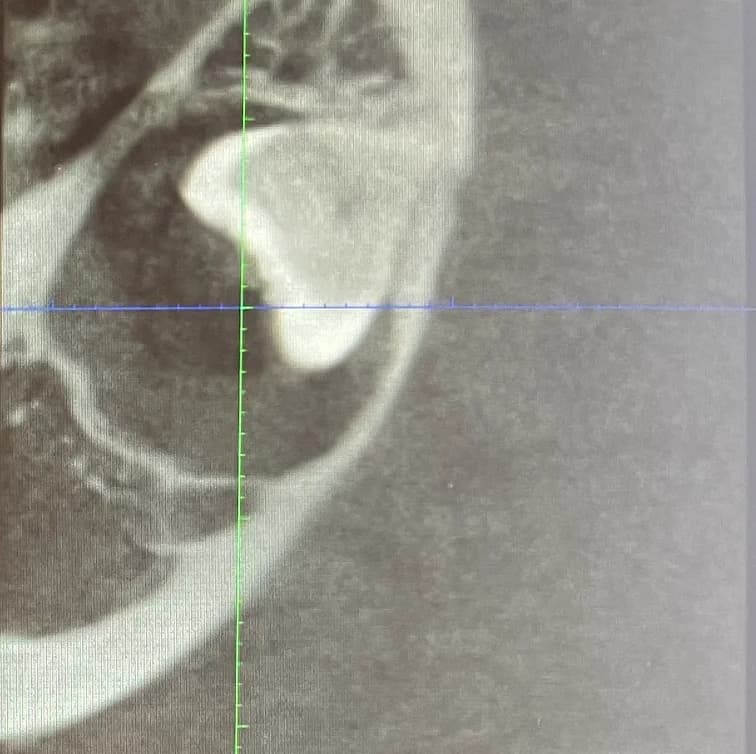

L'extraction des dents de sagesse, également appelées troisièmes molaires, est une procédure dentaire courante effectuée pour enlever les dents qui ne peuvent pas pousser correctement ou qui causent des problèmes dentaires. Elles sont généralement du nombre de quatre et font habituellement leur apparition en bouche entre l’âge de 15 et 25 ans. Elles peuvent faire complètement éruption, être partiellement éruptées ou incluses. Elles n’ont généralement pas assez de place dans la bouche. Ce faisant, elles sont très souvent mal alignées et exercent des pressions sur les dents adjacentes, pouvant même les endommager. L'extraction des dents de sagesse est souvent recommandée lorsque les dents sont incluses (piégées dans la gencive ou l'os) ou qu'elles causent des problèmes tels que la douleur, l'infection, la carie dentaire, le déplacement des autres dents ou le développement de kystes. Il est conseillé de procéder à leur extraction à un jeune âge, généralement à la fin de l’adolescence ou au début de l’âge adulte. Effectivement, les risques s’accroissent avec l’âge et la convalescence est plus aisée à un jeune âge.